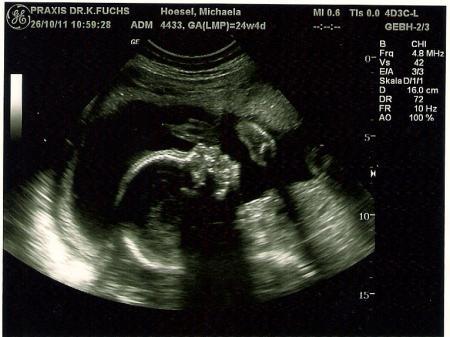

Sehr schön zu sehen wie der Kleine da in meinem Bauch liegt. BEL... Also hat er sich mittlerweile gedreht, seit meinem letzten FA-Besuch. Die arme und Beine schön vor´s Köpfchen gehalten. =)